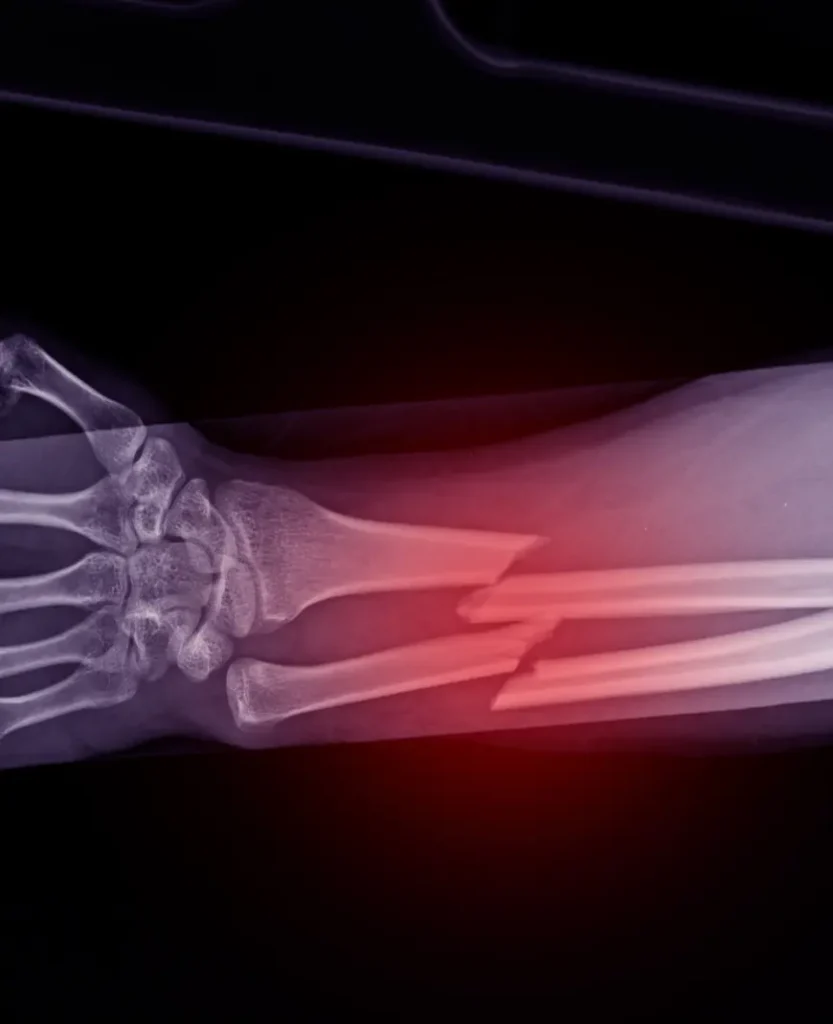

Traumatólogo Ortopedista en Cuernavaca

Dr. Alejandro Alonso

Tratamiento de lesiones comunes:

Traumatología y ortopedia en Cuernavaca

Traumatología y Ortopedia en Cuernavaca

Traumatólogo Ortopedista en Cuernavaca